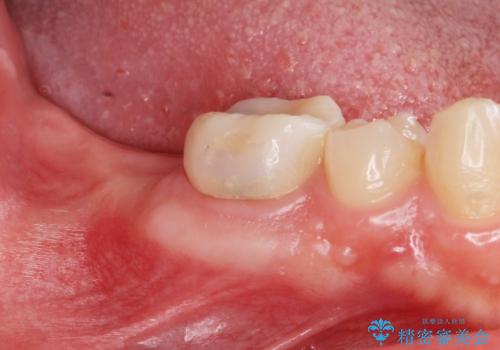

右下の被せ物を外し虫歯を除去したところ虫歯が深く保存が難しい状態だったので抜歯を行いました。

抜歯したところは抜歯後骨の治癒を待ち、CTを撮影しインプラント治療ができる事(骨の厚みなど)確認し治療を行いました。